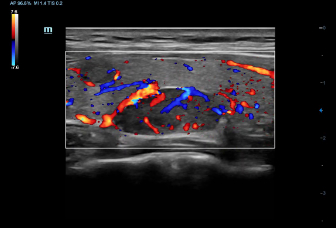

–ě—Ā–Ĺ–ĺ–≤—č–≤–į—Ź—Ā—Ć –Ĺ–į –≥–Ľ—É–Ī–ĺ–ļ–ĺ–ľ –Ņ–ĺ–Ĺ–ł–ľ–į–Ĺ–ł–ł –Ņ–ĺ—ā—Ä–Ķ–Ī–Ĺ–ĺ—Ā—ā–Ķ–Ļ –ļ–Ľ–ł–Ķ–Ĺ—ā–ĺ–≤, –ļ–ĺ–ľ–Ņ–į–Ĺ–ł—Ź Mindray —Ä–į–∑—Ä–į–Ī–ĺ—ā–į–Ľ–į —Ā–ł—Ā—ā–Ķ–ľ—É DC-60 Exp —Ā X-Insight, —á—ā–ĺ–Ī—č –ĺ–Ī–Ķ—Ā–Ņ–Ķ—á–ł—ā—Ć –≤—č—Ā–ĺ–ļ—É—é –Ņ—Ä–ĺ–ł–∑–≤–ĺ–ī–ł—ā–Ķ–Ľ—Ć–Ĺ–ĺ—Ā—ā—Ć –ł —ā–ĺ—á–Ĺ–ĺ—Ā—ā—Ć –≤–ł–∑—É–į–Ľ–ł–∑–į—Ü–ł–ł –≤–ļ—É–Ņ–Ķ —Ā –Ĺ–į–≥–Ľ—Ź–ī–Ĺ–ĺ—Ā—ā—Ć—é, –ł—Ā–ļ–Ľ—é—á–ł—ā–Ķ–Ľ—Ć–Ĺ–ĺ–Ļ –ł–Ĺ—ā–Ķ–Ľ–Ľ–Ķ–ļ—ā—É–į–Ľ—Ć–Ĺ–ĺ—Ā—ā—Ć—é –ł –ĺ–≥—Ä–ĺ–ľ–Ĺ—č–ľ –ĺ–Ņ—č—ā–ĺ–ľ.